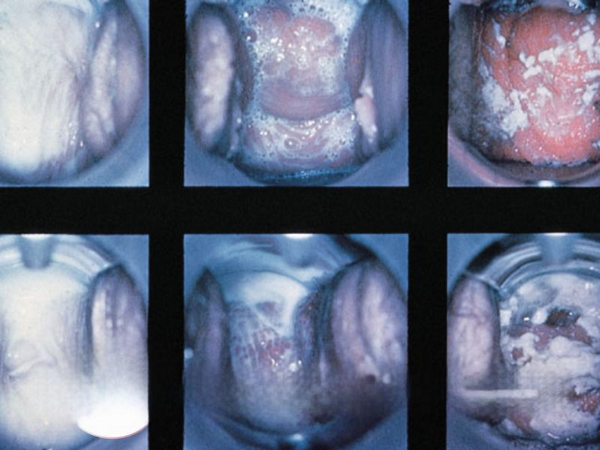

Viêm cổ tử cung – Khi “cửa ngõ sinh sản” bị tấn công

Là tình trạng vi khuẩn, nấm hoặc virus (đặc biệt là HPV) xâm nhập gây viêm nhiễm lớp niêm mạc cổ tử cung.

Mức độ nguy hiểm: Viêm cổ tử cung điều trị muộn dễ dẫn đến viêm lộ tuyến, polyp hoặc ung thư cổ tử cung – một trong những nguyên nhân hàng đầu gây tử vong ở phụ nữ.

Viêm lộ tuyến cổ tử cung – Bệnh “lành tính” nhưng dễ biến chứng

Tuyến cổ tử cung bị tổn thương và lan ra ngoài, tạo môi trường ẩm ướt cho vi khuẩn phát triển.

Mức độ nguy hiểm: Nếu để lâu, các tế bào viêm có thể biến đổi bất thường, tăng nguy cơ ung thư cổ tử cung, gây tắc cổ tử cung và ảnh hưởng đến khả năng thụ thai.